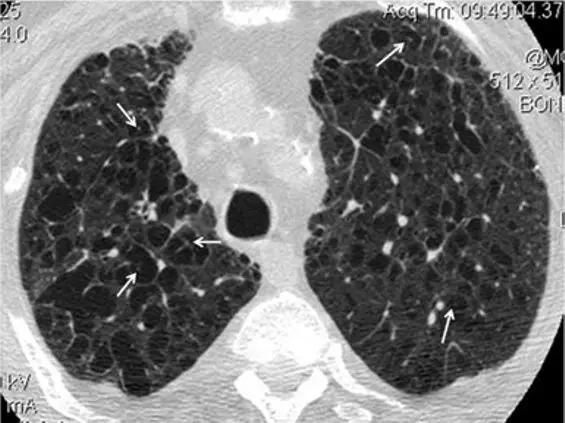

8、囊性病变

囊性模式由界限分明,圆形和外接空气的实质组成,有界限分明的壁和与正常肺。

经典疾病:淋巴管平滑肌肌瘤病(LAM),其特征是通常存在圆形的薄壁肺囊肿,没有在局部明显的特点,分布广泛,包括肋骨角和肺底。 LAM可能伴有胸水表现为胸膜胸腔积液。鉴别诊断是随机分布的囊肿,临床病史表现几乎只影响着育龄妇女。鉴别疾病:是肺组织细胞增生症、淋巴细胞性间质性肺炎(LIP)和小叶性肺气肿。

*LAM。上叶水平的HRCT表现出“囊性模式”,其特征是位于肺实质和隔中的许多大小不等的薄壁“真”囊腔的存在。

肺组织细胞增生症在处于纯囊性期(纯结节性和结节性-囊性期之后的第三期)时模拟LAM。它的特征是存在薄壁和厚壁的囊、形状呈异形,类似于苜蓿叶。囊肿具有特征性以上部和中部肺区分布为主。

*组织细胞增多症。上叶水平的HRCT揭示了一种“囊肿型”,其特征是许多薄或厚的“真”囊肿,形状奇异,大小不一。在右胸膜腔中发现引流导管以治疗气胸,这是这位27岁重度吸烟患者。

淋巴细胞性间质性肺炎 (LIP)可能很少以弥散性肺囊肿为主要HRCT模式(图37)。鉴别诊断中支持LIP的主要发现是与其他辅助发现相关,例如磨玻璃样不透明的弥散性或斑片状区域,不明确的小叶小结节和支气管血管束增厚。此外,引起某种程度的免疫抑制的原发性疾病的临床病史(如干燥病,艾滋病,自身免疫性疾病,蛋白异常)为LIP提供了强有力的线索。

*淋巴细胞性间质性肺炎。上叶水平的HRCT揭示了一种“囊性模式”,其特征是极少的薄壁“真”囊肿,可能具有圆形或更多的分叶形状。免疫抑制的历史(艾滋病,干燥综合征,自身免疫性疾病,蛋白异常)有利于LIP的特异性诊断

小叶中心性肺气肿虽然不存在“真正的”囊,但有时可能会模仿由囊性表现的其他间质性肺疾病。

*中央小叶气肿。HRCT显示在大多数情况下,放射状的小叶中心区没有可辨认的壁(除了小叶间间隔增厚的区域),并且有一个中心白点(在放射线的中心)代表中心小叶动脉(白色箭头) )。中央小叶肺气肿偶发间质性疾病,表现为“真正的囊性病变” 。